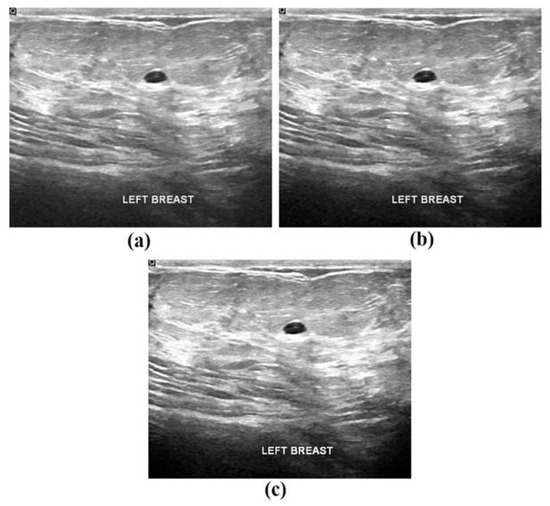

Figure 5 illustrates the sample visualization results of the proposed model during the preprocessing stage. For a given input image, the corresponding noise was removed and the contrast-enhanced images are depicted in the figure. It is evident that the quality of these images was considerably improved in this preprocessing stage.

Figure 5. Sample visualization results: (a) original image; (b) noise-removed image, and (c) contrast-enhanced image.